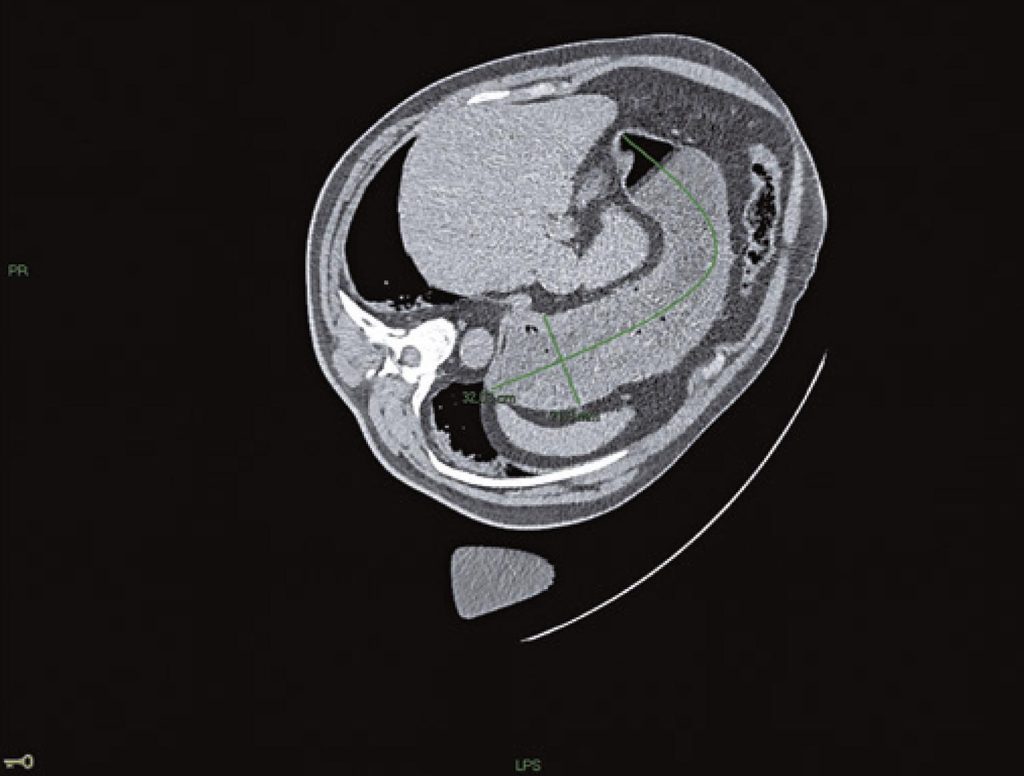

Pulmonary aspiration of gastric residues during anesthesia is a potentially fatal complication for which no specific treatment is available. The primary way to prevent its occurrence in the context of elective surgeries is adherence to fasting protocols. However, some clinical conditions can prolong the gastric emptying time, and the risk of aspiration may exist despite adequate fasting. Recognizing the risk factors for gastroparesis allows the adoption of preventive methods and is the primary way to reduce morbidity and mortality from pulmonary aspiration. In this scenario, the anesthesiologist can investigate the gastric content by using ultrasound, adjust the anesthetic technique, and even postpone elective surgeries. Here, we describe incidental computed tomography finding of solid contents in the stomach of a patient without prior identification of the risk factors for gastroparesis. The patient underwent elective renal nodule ablation under general anesthesia after fasting for 9 hours. During the procedure, solid contents in the stomach were noted on computed tomography. Subsequently, it was discovered that the patient had been using semaglutide for 6 days and had not disclosed this information. Semaglutide use may represent a new and significant risk factor for anesthesia-related pulmonary aspiration. Until studies provide information on the appropriate perioperative management of patients using semaglutide, anesthesiologists need to adopt preventive measures to avoid aspiration. Awareness of this potential association and open communication among patients, physicians, and anesthesia teams are essential for enhancing patient safety.